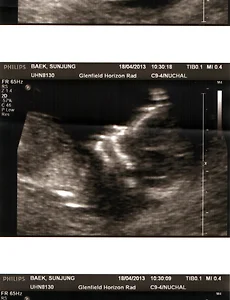

뉴질랜드 생활/다민, Damin's102 기다림. 2013. 6. 17. 남자는 남자끼리.. 요즘 다현이가 자주 하는 말입니다. '남자는 남자끼리' 샤워할 때, 잠잘 때, 놀 때.. 모두 남자는 남자끼리 해야한다고 합니다. 우리집에 남자가 한명 더 생기게 되었습니다. 예상을 깨고 금동이가 남자아이라고 초음파 검사 결과를 받았습니다. 엄마 아빠 모두 여자아이가 태어나길 바랬.. 2013. 6. 7. 금동이 초음파 사진. 4월 18일. 금동이 13주차 4일째. 초음파 찍으러 다녀왔습니다. 다현이 때보다 약간 흥분됨이 덜한게 미안할 뿐입니다.ㅎㅎ 임신을 한 후 출산 할 때까지 특별한 이유가 없다면 3번의 초음파 촬영이 있습니다. 오늘이 그 중 처음입니다. 12주가 지나서 처음이고, 20주가 지난 후 한번 더 그리고.. 2013. 4. 18. 이전 1 ··· 9 10 11 12 다음